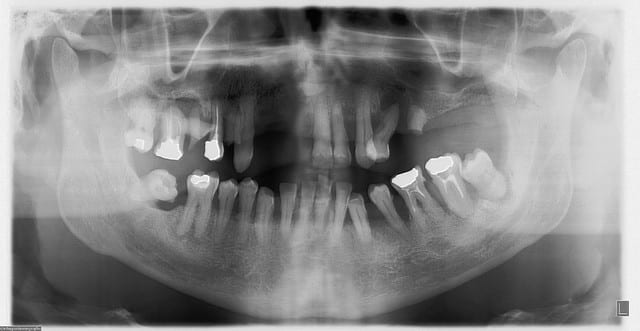

regardes cette radio panoramique par exemple...

petit indice, le "bientôt mci", à ton avis, il reste quoi actuellement (j'ai fait du "ménage")

Je viens de recevoir une pano ton avis.